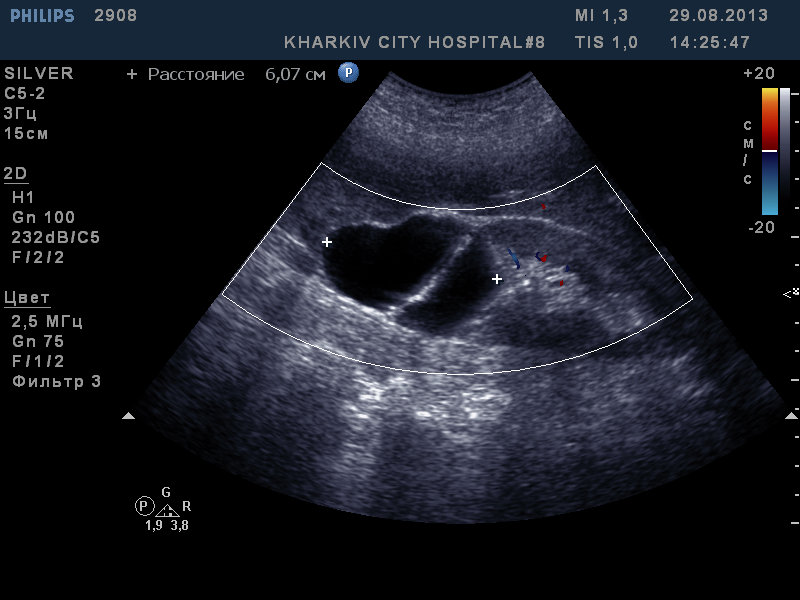

Пожилая пациентка с анемией.

Что по почкам и селезенке? есть ли кровоток в ткани "кисты"правой почки?

Первое впечатление о поражении печени, ЛУ. Осложненная киста/кистозная опухоль правой почки?

Расцениваю как вторичное поражение печени.

селезенка и почки вроде ОК. Киста правой почки. кровоток не лоцировался.

а что за гипоэхогенное образование у желчного?

dok333 писал(а): а что за гипоэхогенное образование у желчного?

Увеличенные ЛУ - метастазы или лимфома, поэтому интересно что с селезенкой.

Еще нужно "пройтись" по толстой кишке - особенно по правому изгибу - поискать СППО

И как в заключении описать ситуацию с ЛУ?

В воротах печени определяются увеличенные лимфоузлы и конгломераты лимфоузлов - до (указать размеры наибольшего).

Конечно же, это повод для выполнения КТ с контрастированием + дообследование желудка и толстой кишки.